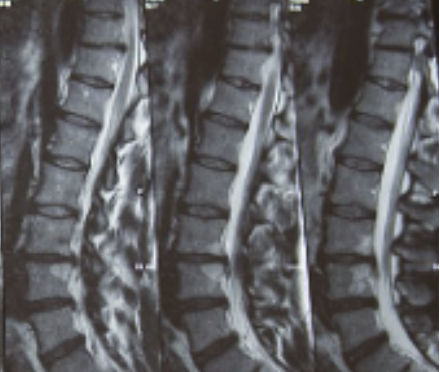

허리디스크는 디스크가 터져서 신경을 누를 경우 생기는 것으로 보통 4,5번에서 많이 발생하고 디스크가 터진 양이 적다면 터진 순간부터 수분이 날아가면서 양이 많이 없어지는데 그렇지 않고 양이 많을 경우 극심한 통증이 생깁니다.

허리디스크를 정확하게 진단하기 위해서는 엑스레이로는 힘들며, MRI를 통해 검사해야 정확하게 볼 수 있습니다.

MRI가 몸에 좋지 않지만 허리 통증으로 엑스레이만 진행할 경우 오진이 많아 지속적인 통증이 계속된다면 허리디스크를 의심하고 MRI 검사를 한번 받아보시길 권유드립니다.